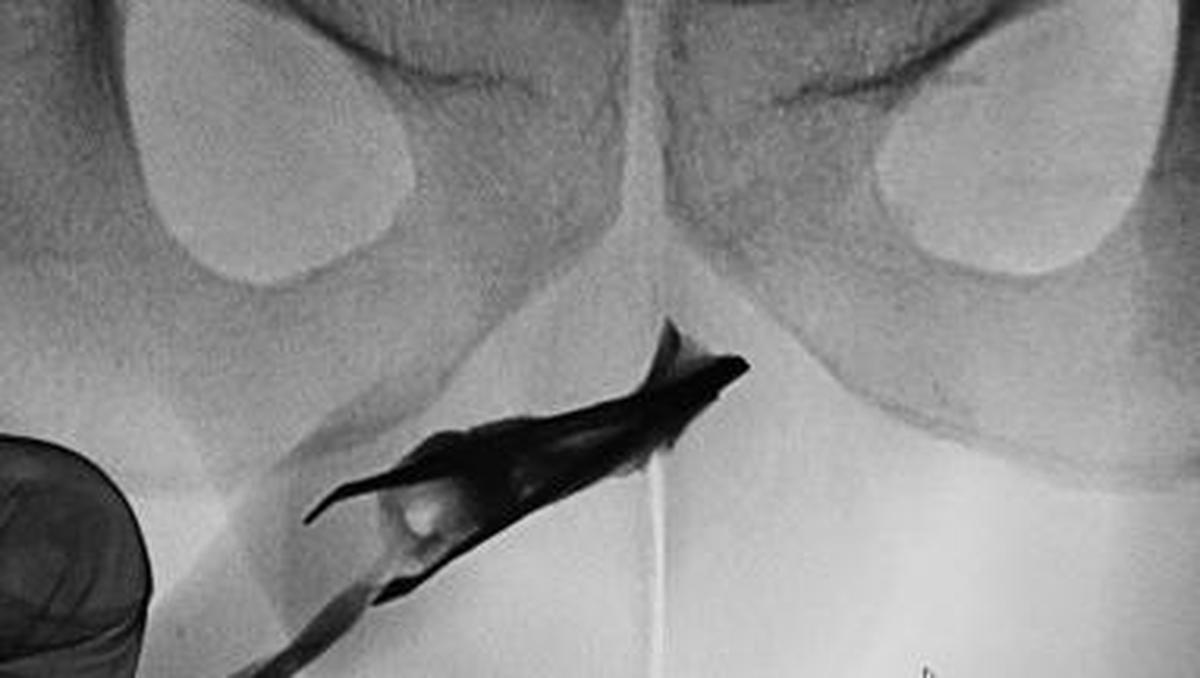

Jakarta – Seorang pasien pria berusia 22 tahun di Arab Saudi datang ke dokter dengan pinset yang menyangkut di penisnya. Benda itu ternyata Sebelumnya ada selama 4 tahun.